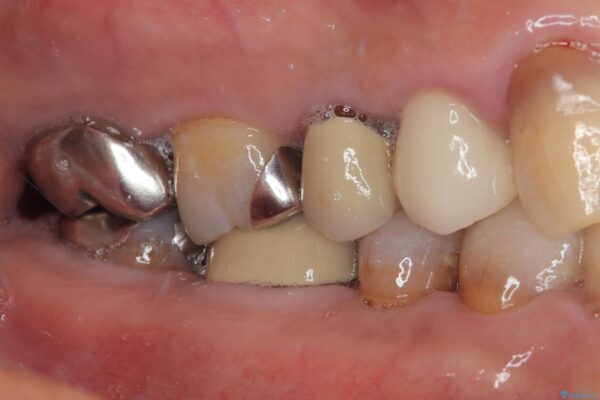

ファイバーコアを築造・精密な支台歯形成と印象採得

治療途中

• 自然な美しさと強度を両立!右上小臼歯の被せもの脱離に対する審美補綴治療 治療前画像